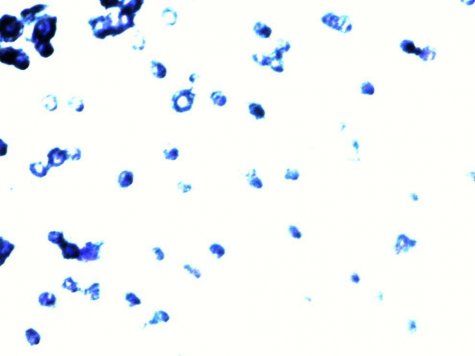

MDA-MB-231细胞在Transwell小室侵袭情况比较,下面三幅图可以看出,对照组侵袭程度较高,FU加改性果胶组侵袭程度要比FU组和对照组低。

对照组

FU 组

FU+小分子果胶下面几幅为划痕实验,结果证明改性果胶和5-氟尿嘧啶联合使用可以有效抑制肿瘤细

胞的远端转移情况。